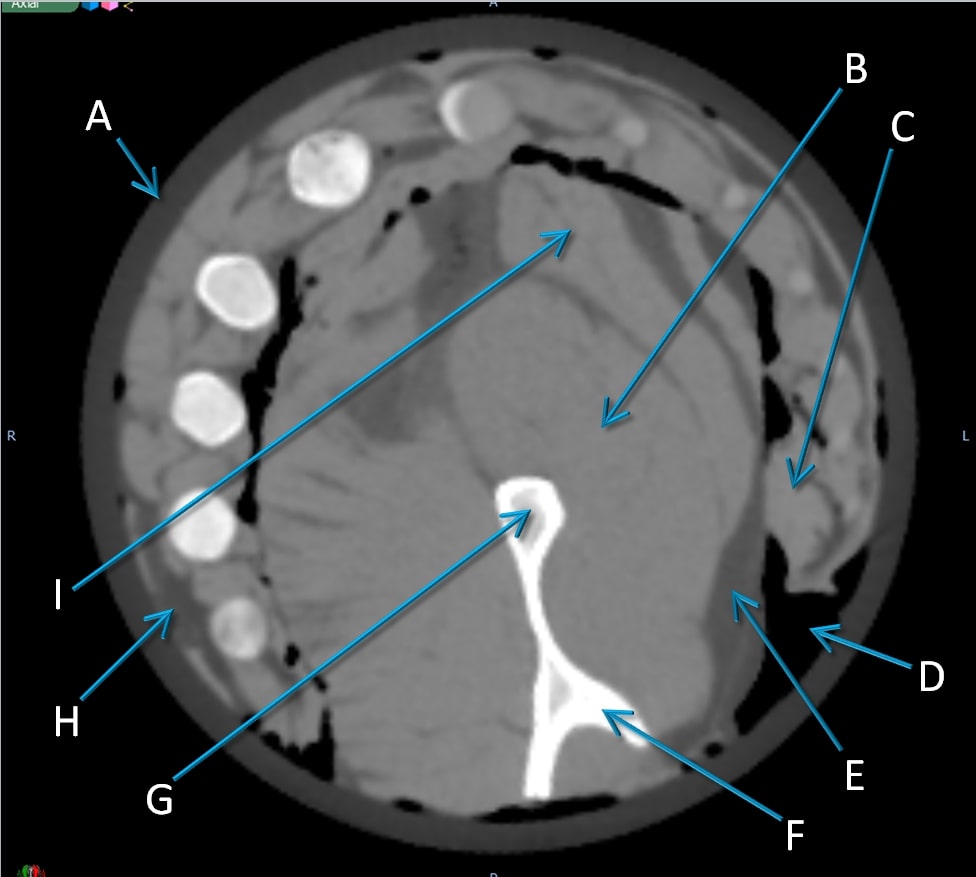

Examples of regions for one slice each in three views of the pig’s head are indicated in Fig. 6, and RSP comparisons between the pCT and the three x-ray CT scans are in Table 3. A close up axial view of the tympanic bullae is shown in Fig 7, which illustrates that the tympanic bullae ROI encompasses a heterogeneous mixture of pneumatized cells separated by thin bony septa. The high and low dose horizontal CT RSPs are consistent within 0.5%. The vertical x-ray CT scan generally shows similar results, although with differences of 2% for brain stem and skull relative to the horizontal scans. Ignoring the RSP differences for sinus air, which are insignificant in absolute terms, the largest difference between pCT and x-ray CT is for the bullae, (-29% to -41%), followed by skull (-2.4% to -4.3%) and brain stem (-2.2% to -4.4%). All other RSP differences (n=24 for 8 tissues) range from -2.5% to +2.1% with a mean of -0.4%. With the exceptions of tongue and lens, the differences for these eight tissues are negative or zero.

Fig. 8 shows a comparison of the average of ten 1 mm sagittal slices from a lateral region of the pig’s head for pCT and the vertical x-ray CT, in order to reduce noise. Features are slightly blurred due to their change in shape with depth. The grey scale reflects the measured RSP, whereas in Fig. 6 and 7 the grey scales were windowed and levelled to optimize contouring. The largest differences are in regions of heterogeneity such as the teeth and tympanic bullae.

The difference map also clearly shows the systematic discrepancy in the skull and the mandible, while soft tissue regions such as brain and muscle regions show closer agreement. The difference in the tip of the snout is caused by an incomplete set of pCT data through that area. The pencil beam scans used for the pCT data set only covered a cm2 area, so the tip of the snout was not quite covered at lateral angles.